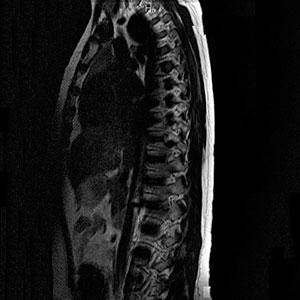

Магнитно-резонансная томография (МРТ) позвоночника представляет собой высокоэффективное неинвазивное исследование, позволяющее получить детальную информацию о твердых и мягких тканях осевого скелета. Этот метод визуализации основан на измерении электромагнитного отклика атомных ядер, после чего данные преобразуются в трехмерное изображение.

Магнитно-резонансная томография (МРТ) позвоночника предоставляет ценную информацию при исследовании межпозвоночных дисков, суставов, нервных стволов, артерий, кровеносных сосудов, спинного мозга и других анатомических структур.

Что может продемонстрировать МРТ пояснично-крестцового отдела позвоночника? Это диагностическое исследование позволяет получить сведения о состоянии и строении позвонков, оценить взаимное расположение анатомических элементов, изучить межпозвоночные суставы и отверстия, определить подвижность отдельных сегментов позвоночника, степень искривления осевого скелета, а также локализацию и характер механических повреждений.

Кроме того, с помощью магнитно-резонансного исследования можно уточнить форму, диаметр, характер, особенности расположения и степень распространения патологического процесса. В случае отсутствия патологий результаты МРТ демонстрируют изображения здорового позвоночника.